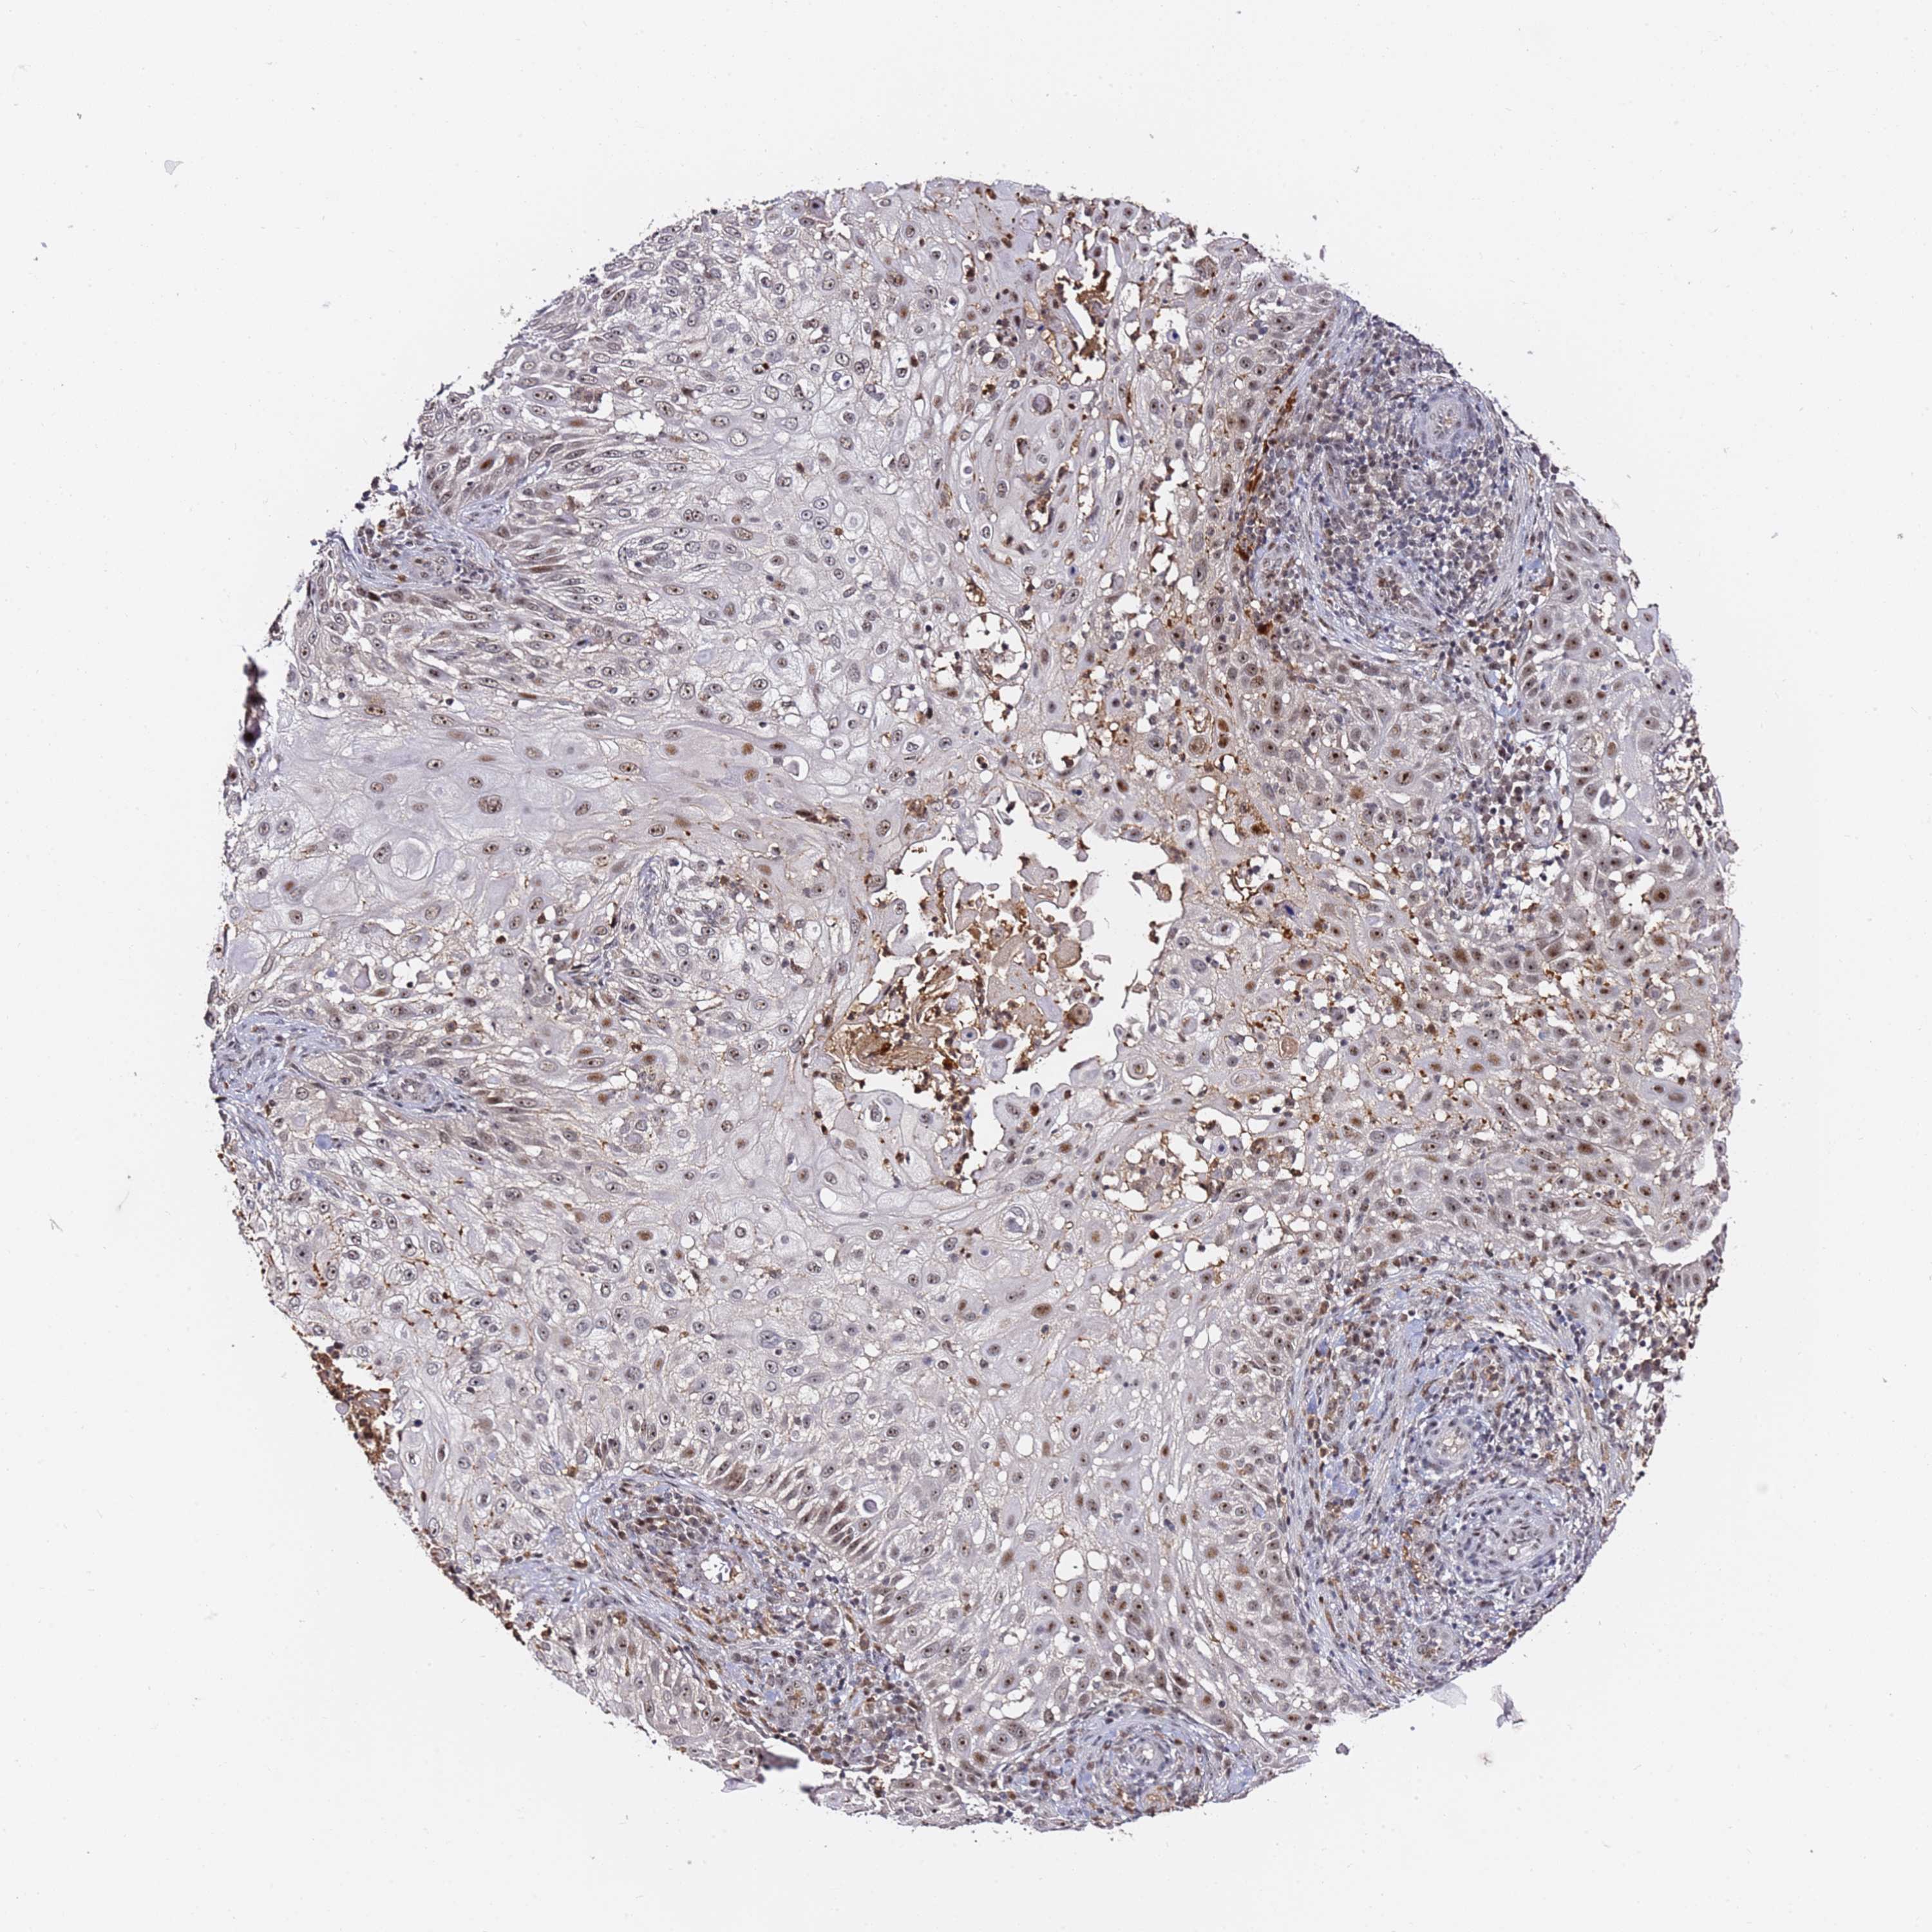

SKIN CANCER - Protein expressioni

A mouse-over function shows sample information and annotation data. Click on an image to view it in a full screen mode. Samples can be filtered based on level of antibody staining by selecting one or several of the following categories: high, medium, low and not detected. The assay and annotation is described here.

Each image is clickable and will lead to virtual microscopy that enables deeper exploration of all samples and also displays staining intensity scores, fraction scores and subcellular localization as well as patient and tissue information for each sample.

Antibody HPA046681

Staining

Medium

Intensity

Moderate

Quantity

75%-25%

Location

Cytoplasmic/membranous,nuclear

Squamous cell carcinoma, NOS